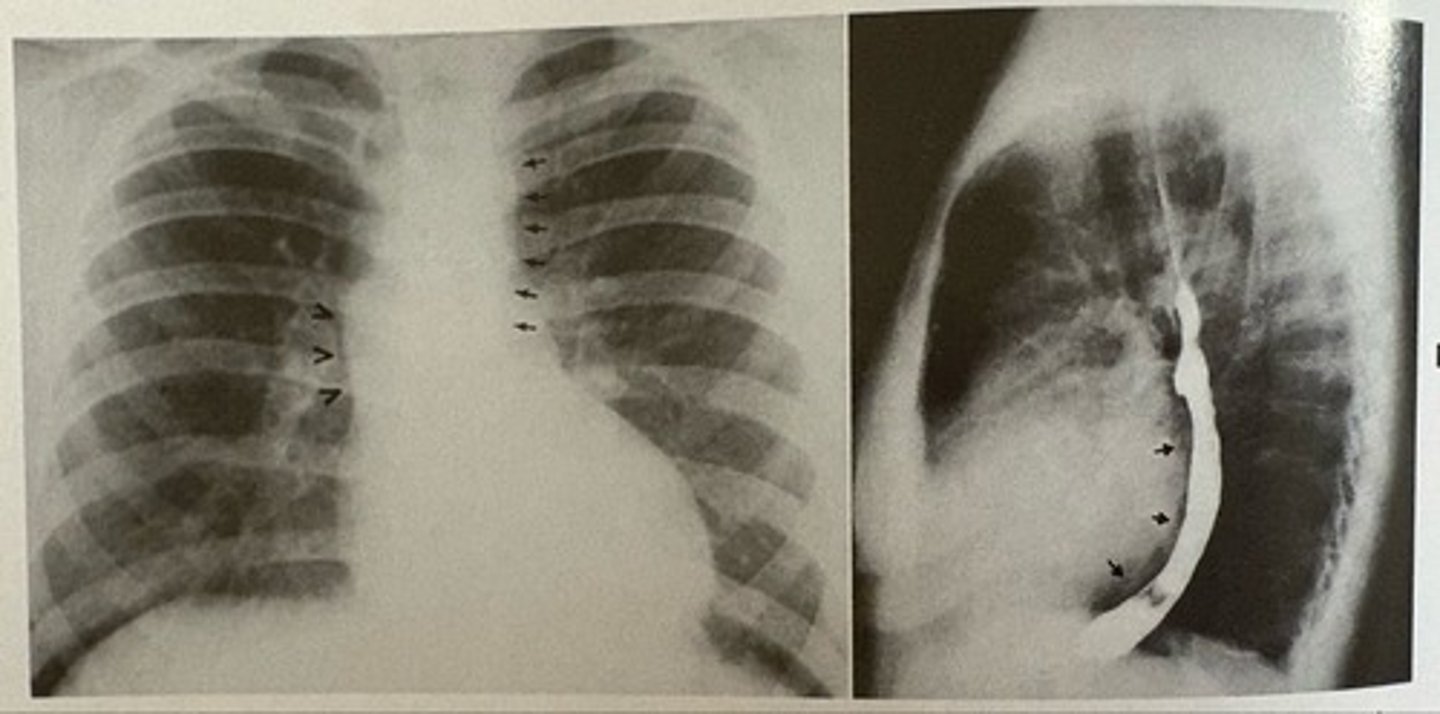

interstitial pulmonary edema

what pathology is present?